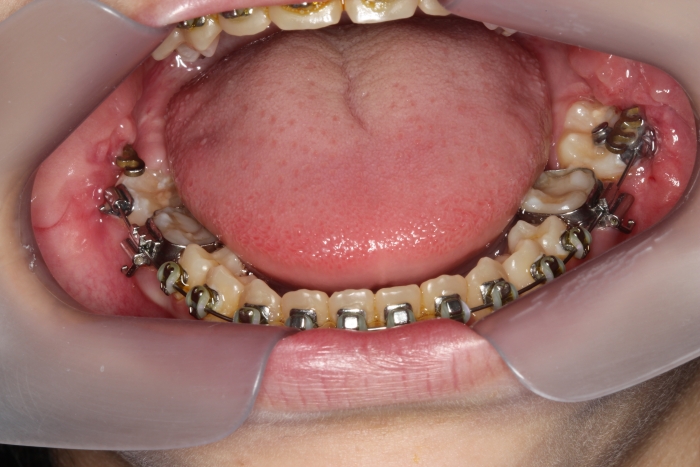

Oclusal inferior com segundos molares em posição inadequada - Clínica Cliniface

Oclusal inferior com segundos molares em posição inadequada